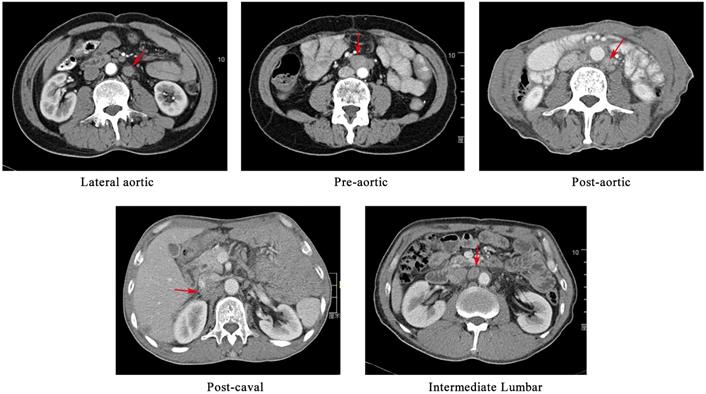

The preoperative workup, surgical procedure and follow-up of the patients were described elsewhere [8, 9]. The suspected metastatic LNs were reviewed by an experienced radiation oncologist and a radiology expert. The positive nodes were identified on the basis of the following features, as described in the previous study[10, 11]: (1) round shape with a short axis length of ≥1 cm; (2) presence of an infiltrative margin; (3) continuous increase in number and size compared with those in the previous images; (4) presence of central necrosis or non-homogeneous enhancement; (5) LNs with SUVmax value of >2.4 in the PET/CT images; and (6) responsive to anti-cancer treatment. In cases in which patients had more than one follow-up scans, we analysed the first record with positive findings. The PALNs based on the previous study were grouped into left lumbar LNs (including pre-aortic, lateral aortic and post-aortic LNs), intermediate lumbar LNs and right lumber LNs (including precaval, lateral caval and postcaval LNs) [12]. The CT-based illustration of the LNs was shown in Figure 1.

Figure 1

A CT-based illustration of the classification of the metastatic para-aortic lymph nodes.

A total of 248 nodes were considered malignant. The locations were summarised in Table 2 and shown in Figures 2 and 3. The three most frequent metastasis sites were the lateral aortic region (48.39%), pre-aortic region (22.58%) and intermediate region (19.35%). Sixty-two (95.38%) patients showed left lumbar LNs metastasis (with a median number of 2), and 37 (59.68%) of them had concurrent intermediate or right lumbar LNs metastasis (with a median number of 1). Twenty-eight (43.08%) patients presented PALN metastases with celiac LN failures. The median short axis of the left, intermediate, and right lumbar LNs was 1.25 mm, 0.97 mm, and 1.09 mm, respectively.